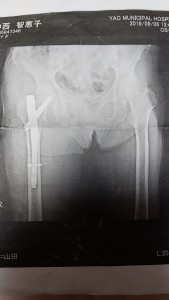

祖母骨折。

祖母が転倒し、骨折しました😅

99歳の誕生日を目前にした日でした。

右の大腿骨の転子間骨折ですかね😅

早く元気になってほしいです✨

そして、白寿のお祝いさせとくれ✨